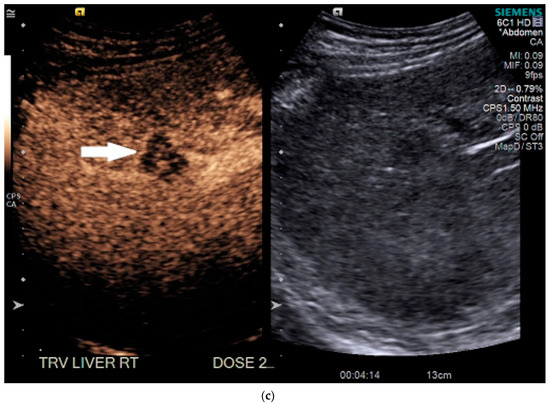

On grayscale US, a subtle 1.2 cm hypoechoic focal area was identified on a background of echogenic, heterogeneous liver echotexture (Figure 3). This area was targeted with contrast, which showed avid arterial-phase enhancement, and rapid, but mild washout (Figure 3). This was also designated LI-RADS M due to the early washout. CT was performed to confirm the finding and initially, the lesion was not identified by the radiologist, despite a diagnostic late arterial phase. On closer inspection with the US finding in mind, subtle enhancement and washout on the CT was seen and considered LI-RADS 4 (Figure 4), and due to this designation and its small size, a shorter interval follow-up was performed at 3 months rather than 6 months.

Figure 3.

Patient 2 ultrasound images, with liver lesion denoted by black arrow: (a) grayscale images showing the hypoechoic lesion. Post contrast administration ultrasound in arterial phase (b) and early washout (c) of the lesion, LI-RADS M.

Figure 4.

Patient 2 CT images using liver windows to highlight the lesion seen on CEUS (white arrow): (a) late arterial phase axial contrast-enhanced CT; (b) 3 min delayed phase.

The patient indeed followed up with an additional four-phase CT 3 months later, and the lesion had grown and was then clearly evident (Figure 4). It was upgraded to a LI-RADS 5, and the patient proceeded to treatment with a successful TACE. However, follow-up CTs over the next 6 months demonstrated development of new LI-RADS 5 lesions, which were subsequently treated with an additional TACE.